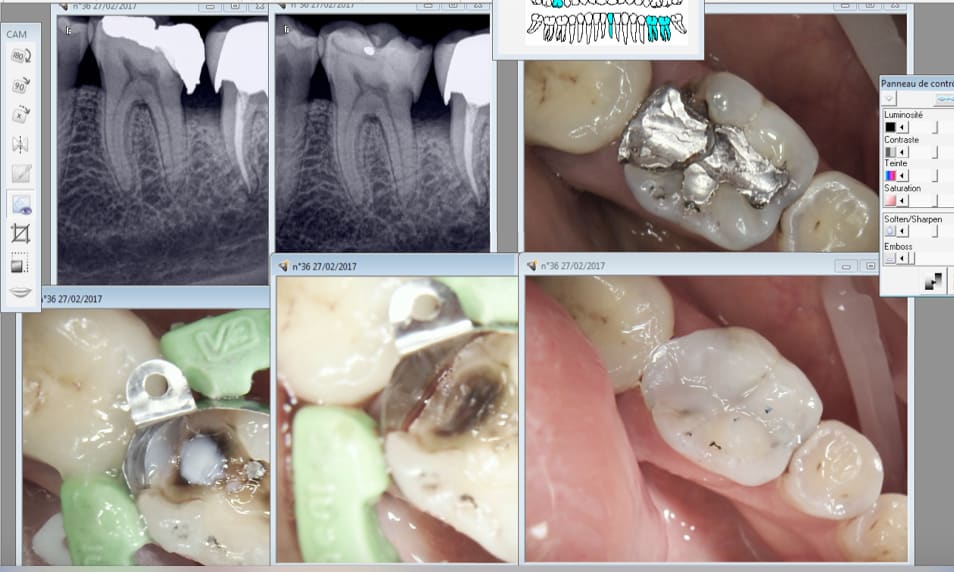

27/02/2017 à 19h32

Je fidélise. -)

Oh mais c'est plus joli Dr. merci !

De rien. A la prochaine ! -))))